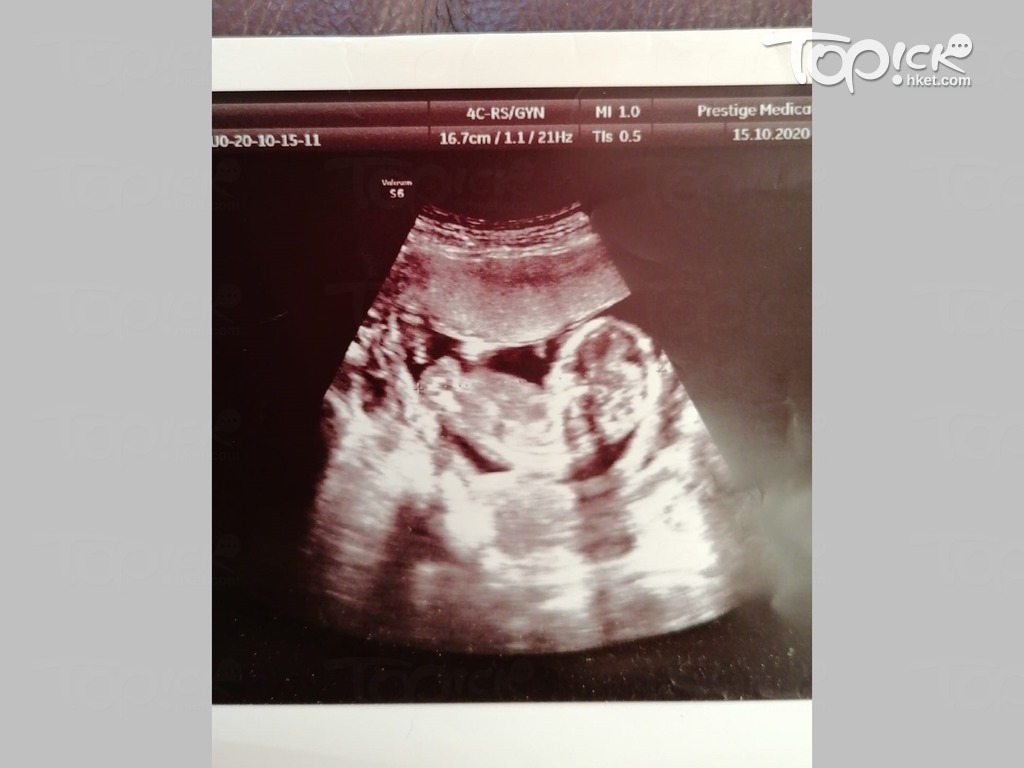

直至22周产检,医生突然告知腹中爱女患有巴陶氏症,即多了1条第13号染色体,患者会出现多种身体缺憾,「首先是小脑比正常细、下巴也有点小,横隔膜穿了一个洞、胃又上移、压住肺部,肾的大小也有不同......医生还说:「你们信教的?我都信教,但我告诉你,不可能有神迹。」